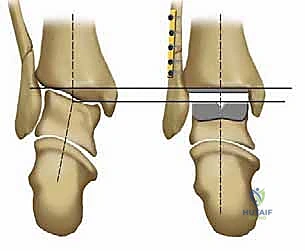

1. نظام سالتو لمفصل الكاحل الكلي (Salto Total Ankle Prosthesis - Mobile Bearing)

* التصميم الميكانيكي: يُعرف بأنه نظام ذو "مكون متحرك" (Mobile-bearing). يتكون من ثلاثة أجزاء رئيسية:

1. مكون معدني يثبت في أسفل عظمة الساق (Tibia).

2. مكون معدني يثبت في أعلى عظمة الكاحل (Talus).

3. قطعة بلاستيكية من البولي إيثيلين عالي الكثافة (Polyethylene insert): هذه القطعة ليست ثابتة، بل تنزلق بحرية بين المكونين المعدنيين.

* الميزة الكبرى: هذا التصميم يسمح بـ "التموضع الذاتي" (Self-alignment). أثناء الحركة، تتحرك القطعة البلاستيكية لتتكيف مع القوى الميكانيكية، مما يقلل من الضغط الواقع على واجهة التثبيت بين المعدن والعظم، ويحاكي حركة الكاحل المعقدة بشكل رائع.

* التثبيت: هو مفصل "غير إسمنتي". يتم تغطية الأسطح المعدنية الملامسة للعظم بطبقة مسامية من التيتانيوم وهيدروكسي أباتيت (Hydroxyapatite). هذه الطبقة تشجع العظم الطبيعي للمريض على النمو داخل مسام المفصل (Bone Ingrowth)، مما يوفر تثبيتاً بيولوجياً صلباً يدوم لسنوات طويلة.

2. نظام سالتو تالاريس (Salto-Talaris Prosthesis - Fixed Bearing)

بناءً على النجاح الهائل لنظام سالتو، تم تطوير نظام سالتو تالاريس لتلبية متطلبات مدارس جراحية مختلفة (خاصة في الولايات المتحدة).

* التصميم الميكانيكي: يشارك هذا النظام نفس الهندسة التشريحية الممتازة للمكونات المعدنية لنظام سالتو، ولكن مع اختلاف جوهري واحد: المكون البلاستيكي (البولي إيثيلين) هنا ثابت (Fixed-bearing) ويتم قفله بإحكام داخل المكون المعدني العلوي (الظنبوبي).

* الفلسفة وراء التصميم: أثبتت الأبحاث وخبرة الجراحين، بما في ذلك الأستاذ الدكتور محمد هطيف، أنه إذا تم إجراء القصات العظمية أثناء الجراحة بدقة متناهية تتوافق مع التشريح الطبيعي، فإن الحاجة إلى حركة واسعة للمكون البلاستيكي تقل بشكل كبير.

* الميزة الكبرى: نظام سالتو تالاريس يوفر استقراراً